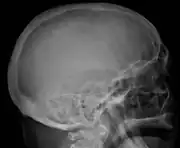

The diagnostic examination of a person with suspected multiple myeloma typically includes a skeletal survey. This is a series of X-rays of the skull, axial skeleton, and proximal long bones. Myeloma activity sometimes appears as "lytic lesions" (with local disappearance of normal bone due to resorption). And on the skull X-ray as "punched-out lesions" (pepper-pot skull). Lesions may also be sclerotic, which is seen as radiodense.[47] Overall, the radiodensity of myeloma is between −30 and 120 Hounsfield units (HU).[48] Magnetic resonance imaging is more sensitive than simple X-rays in the detection of lytic lesions, and may supersede a skeletal survey, especially when vertebral disease is suspected. Occasionally, a CT scan is performed to measure the size of soft-tissue plasmacytomas. Bone scans are typically not of any additional value in the workup of people with myeloma (no new bone formation; lytic lesions not well visualized on bone scan).

Skull X-ray showing multiple lucencies due to multiple myeloma